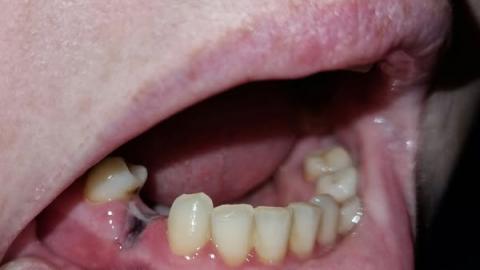

Based on the photos (zoomed and reviewed from multiple angles): there is a partially healed/missing-molar area in the lower jaw with a thin, whitish/gray string-like band or tissue running between the back area and the adjacent teeth. The adjacent gums look slightly inflamed. The patient reports pain and bad smell. This most commonly represents a localized infection or retained foreign material (food, suture/retraction cord fragment, bone sequestrum) with secondary gum inflammation and possible sinus tract formation.

Missing or heavily restored posterior molar region visible.

A pale/gray fibrous strand or material bridging the extraction/defect site to the adjacent tooth.

Localized gingival redness and mild swelling.

Evidence of plaque/debris on adjacent teeth that could feed infection.

Malodor reported by patient — suggests bacterial activity/decay or draining infection.